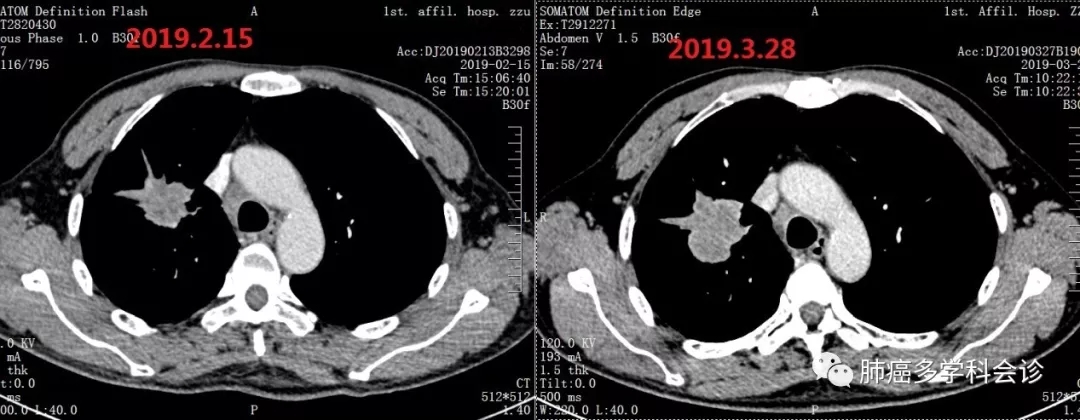

3.webp.jpg11.webp.jpg治疗4个周期后复查,原发灶较前有所增大:

第二次参加肺癌多学科会诊。鉴于停止化疗后、PD-1抗体治疗期间未再发生呕血和其他出血情况,专家组建议在现有PD-1抗体的基础上联合阿帕替尼。

自2019.3.29起,在PD-1抗体(SHR1210)治疗基础上增加阿帕替尼口服,持续至2019-06-29。口服阿帕替尼后头面部和胸背部的反应性毛细血管增生症(过去称为樱桃样血管瘤)完全消退。体重恢复至患病前水平,PS 0-1分。肺原发灶进行性缩小: